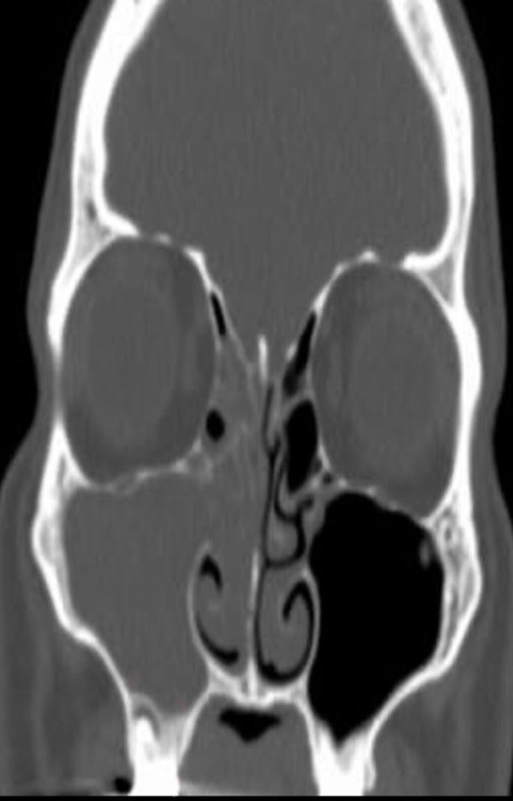

Modality CT paranasal sinuses (coronal plane)

Findings right maxillary sinus is completely opacified. Extensive soft tissue density material is also present in the ipsilateral nasal cavity and the right ethmoid sinus is nearly completely opacified.

Diagnosis acute sinusitis